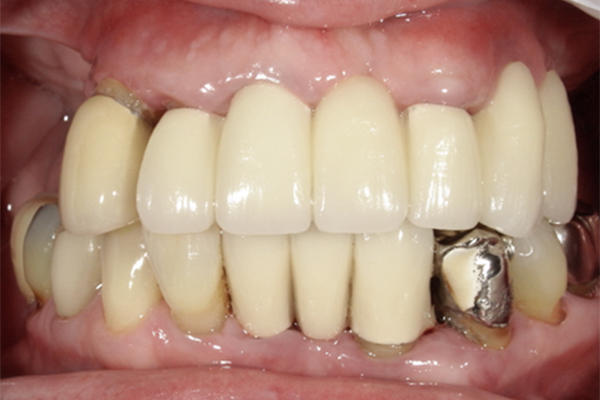

| 主訴 | 全体的にきれいにしたい |

|---|---|

| 治療内容 | 午前中に上下顎共に重度の歯周病、虫歯のため全ての歯を抜歯させていただき下顎はインプラントの土台を3本埋入し歯型を取り午後に上部構造(下顎全ての歯)を装着、上顎は一度総入れ歯を装着させていただきました。 治療が1日で完了しその日のうちに噛めるようになります。 |

| 治療期間 | 2回(1回目に資料取りをさせていただき2回目に下記の全ての治療をさせていただきました。) |

| 治療費 | 250万円 |

| 治療 リスク | 抜歯した部位などに関しては当日痛みが出ますので痛み止めなどを処方させていただきます |